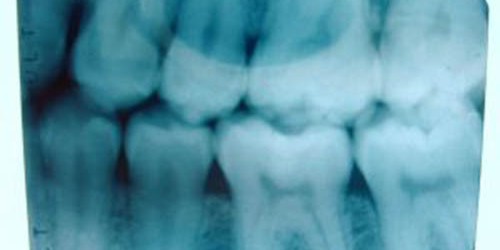

I am scheduled to have oral surgery next week because of impacted wisdom teeth. I have to have them removed surgically because it started causing me pain and doctor told me that gum infection can develop from that condition. I’m 22, female. I’ve never had oral surgery before. I guess that this one is necessary. I’m not sure how this happened to my teeth and how dangerous it is.

It is more common situation that wisdom teeth get entrapped between the jaw bone and gums, then to develop in proper alignment. It is important to have them removed because impacted wisdom teeth can cause permanent damage of nearby gums, jaw bone and teeth. This surgical procedure is very routine as I know, I had it 3 years ago, and also had these teeth removed. The most uncomfortable in oral surgery as I think is feeling that left after anesthesia, but it is really temporal.